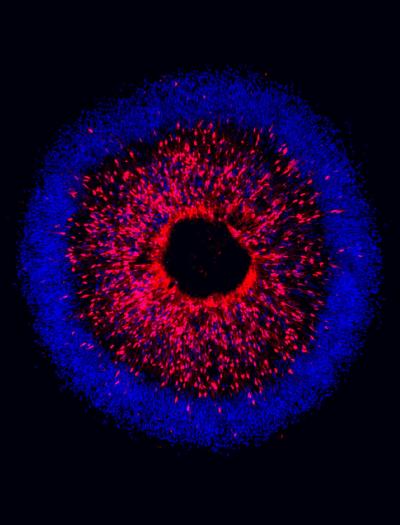

Image of fluorescent cells in iris-like pattern

Image credit: IU School of Medicine